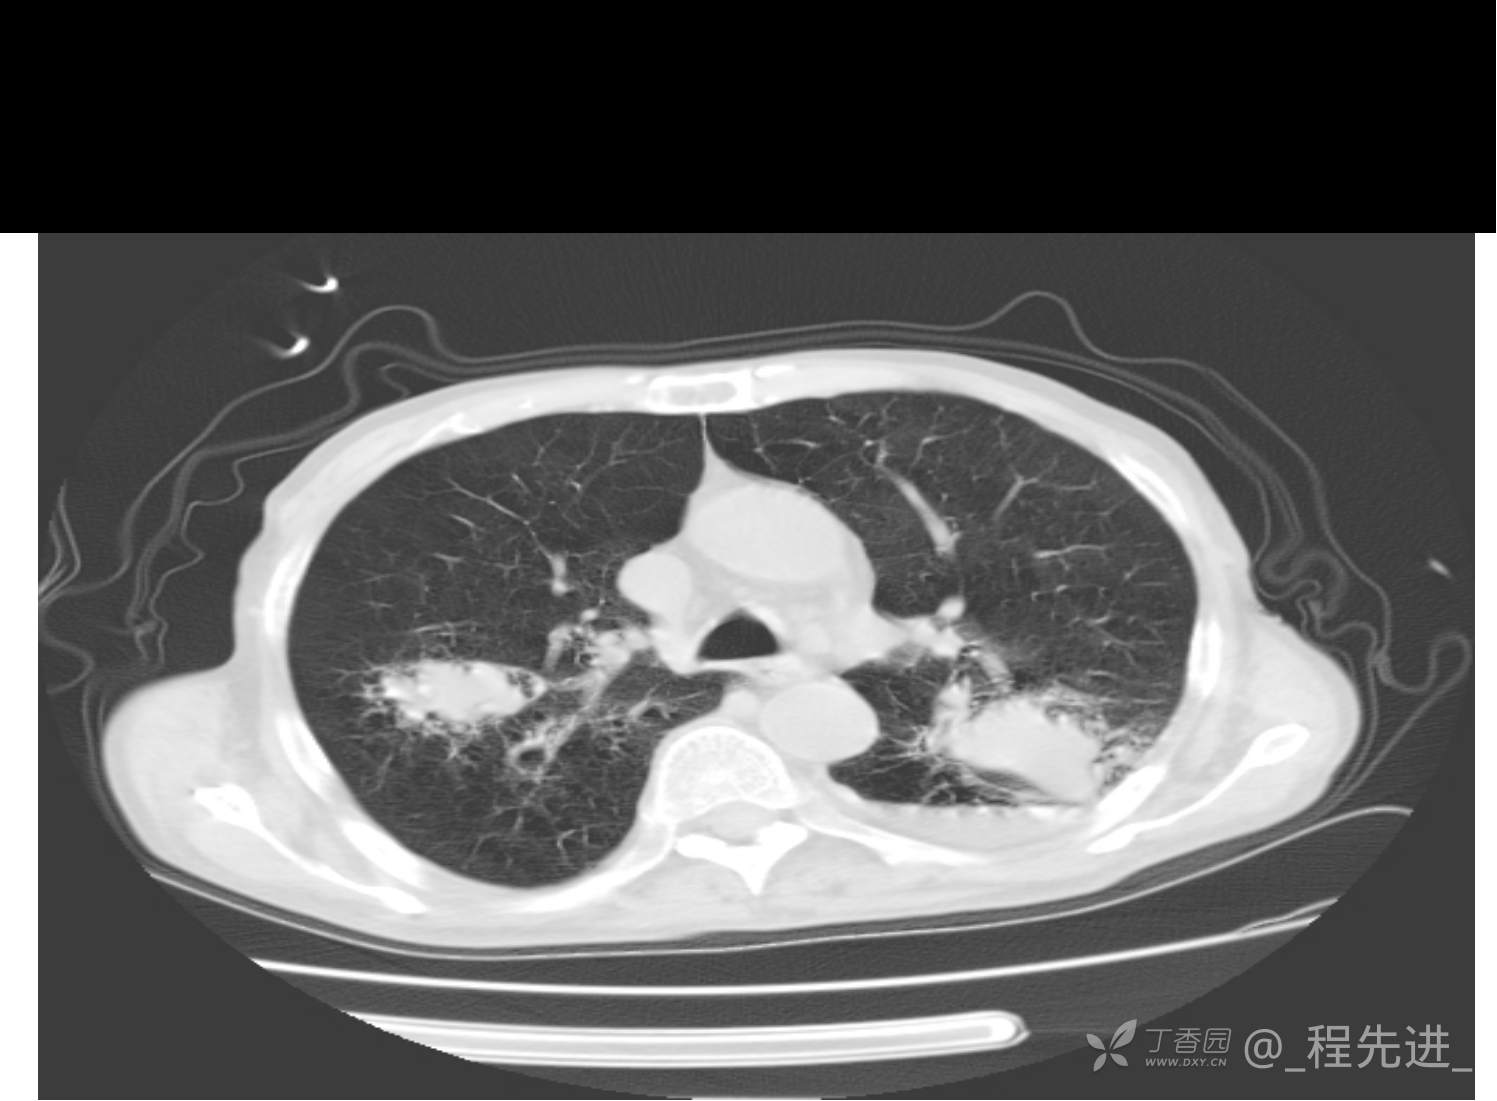

患者性别:男

患者年龄:81岁

简要病史:反复咳嗽、咳痰20余年,加重1周。两肺呼吸音低,可闻及散在干湿啰音。